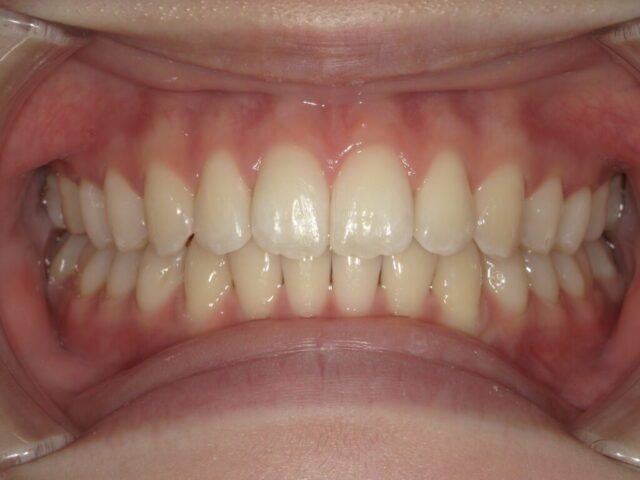

8歳から始める、健やかな土台作り

小児矯正

| 診断名 | 出っ歯(上顎前突)、深い噛み合わせ(過蓋咬合)、すきっ歯(正中離開) |

| 年齢・性別 | 8歳 |

| 治療期間・回数 | 2年10ヵ月 |

| 治療方法 | 上下拡大床、上唇小帯切除術、バイトプレート、前歯部ブラケット |

| 費用 | 440,000円(税込) |

| デメリット・注意点 | 最初は装置に違和感を覚えることがありますが、1週間ほどで自然に慣れていきます。 |